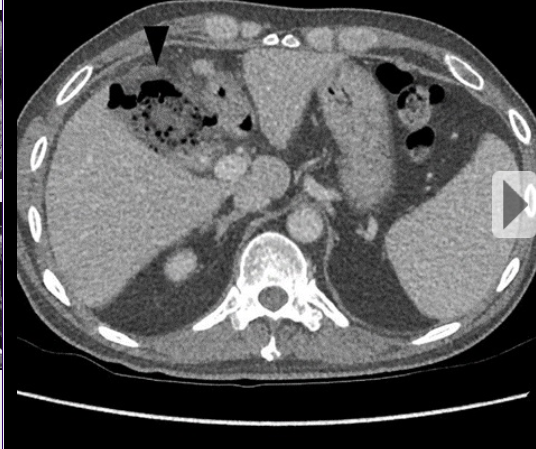

Homem, 57 anos, história de pancreatite crônica

Pseudoaneurisma da artéria mesentérica superior

Separação da camada média e da adventícia na parede da artéria (diferente do aneurisma, que seria a dilatação das três paredes do vaso). Pode ocorrer por aterosclerose, trauma, inflamação (como neste caso).

Pode estar associado à ruptura (pseudoaneurisma tem risco muito maior que de um aneurisma).